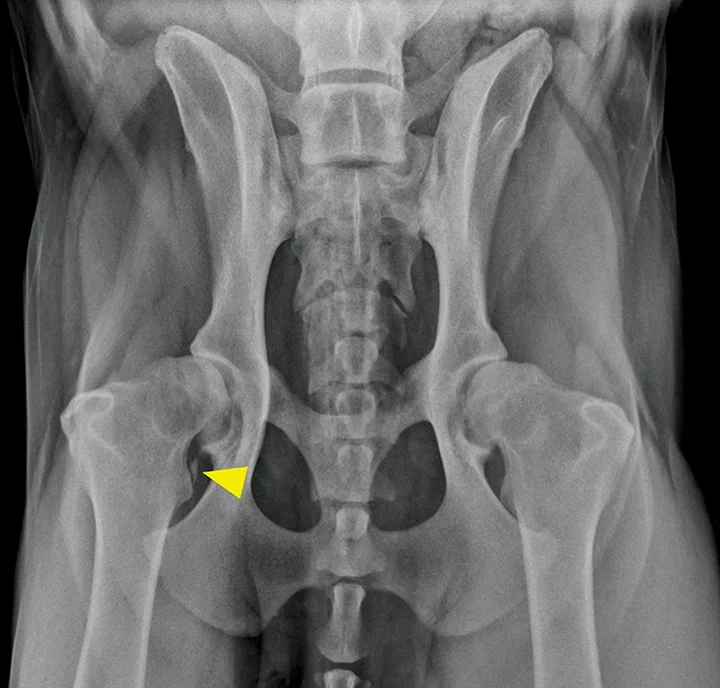

Arthroscopic image of the shoulder joint of a dog with biceps tenosynovitis. The biceps tendon (B) originates on the supraglenoid tuberosity of the scapula (A) and traverses distally through the bicipital groove of the humerus (closed arrowheads). Synovitis and increased vascularity of the tendon sheath are present (open arrowheads).